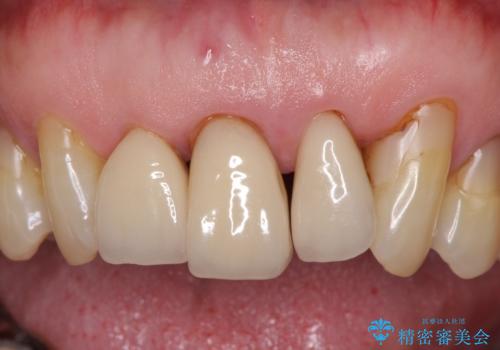

上の歯は見た目を良くしたいというご希望があったため、歯周外科処置を行った歯についてはセラミッククラウンで補綴することとしました。

気になっていた歯の痛みや歯肉からの出血がなくなり、改善したいと思っていた外見も綺麗に仕上がり、大変満足していただきました。